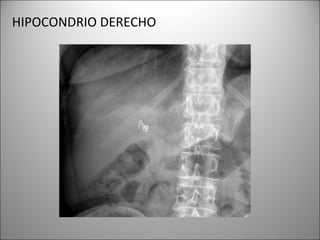

HIPOCONDRIO DERECHO

HEMIDIAFRAGMA

BASES PULMONARES